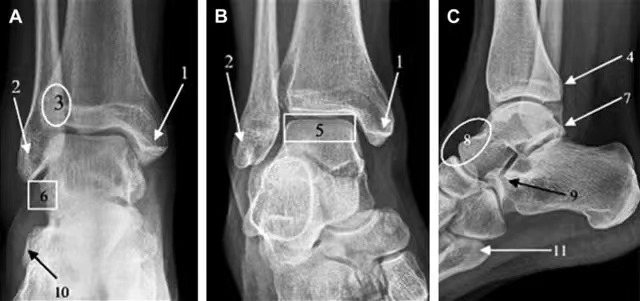

(7)踝部骨折脱位

距骨骨折脱位:多由高处跌下所致,压痛点在距骨,X线片可协助鉴别。

踝部韧带损伤:多由踝关节扭伤所致,肿痛,压痛点在内踝下方或外踝的前下或下方,无骨擦音和畸形;X线摄片可排除骨折。

(8)距骨骨折

踝部骨折:压痛点在内或外踝,有畸形和骨擦音;X线摄片可协助诊断。

跟骨骨折:高处跌下所致,足跟部有瘀斑、压痛,骨折移位严重出现扁平足,后跟增宽;X线摄片可鉴别。